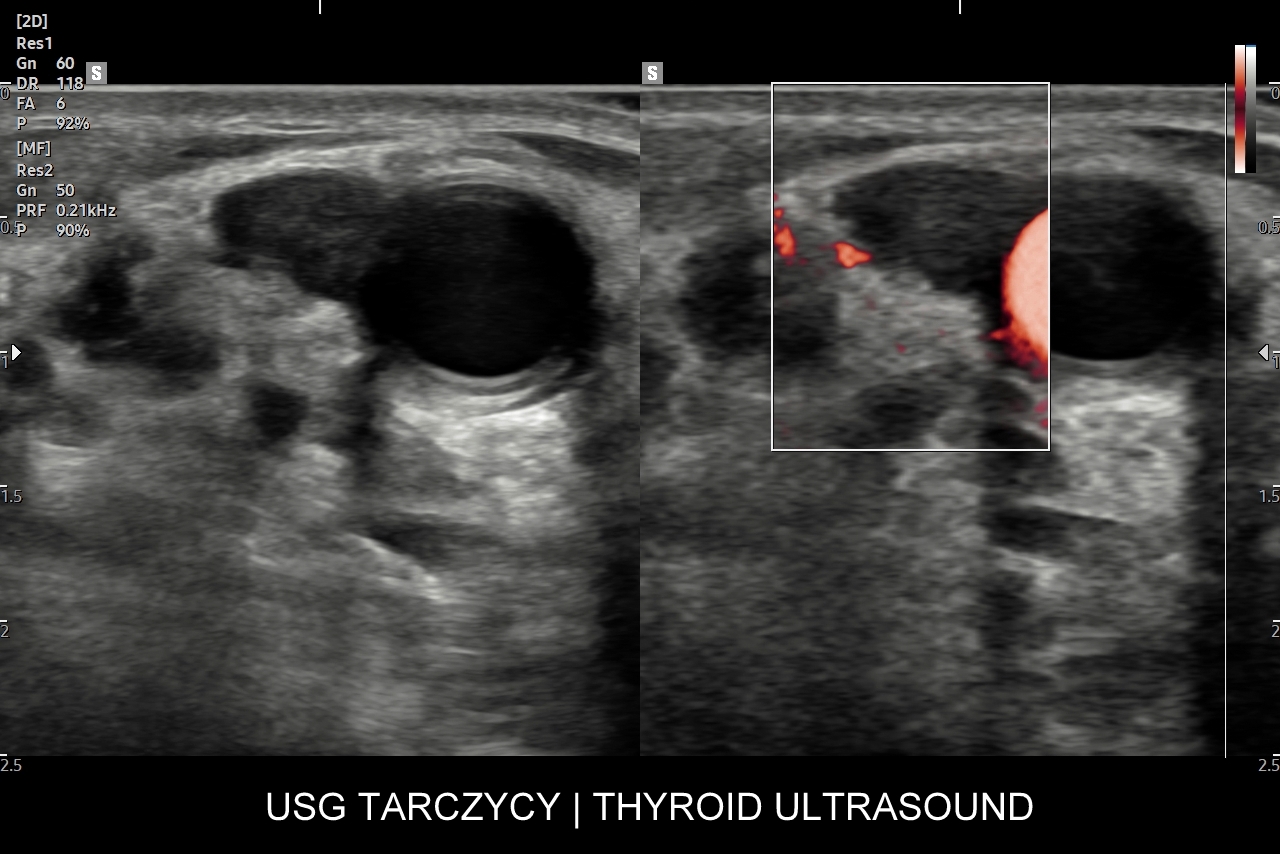

W Interdyscyplinarnej Pracowni USG dr Tomasza Szczepańskiego istnieje możliwość przeprowadzenia wysokospecjalistycznej oceny gruczołu tarczowego w postaci multiparametrycznego badania MPUS tarczycy, które wykonywane jest na zaawansowanym technologicznie aparacie USG przy wykorzystaniu modalności zwiększających rozdzielczość obrazowania zmian chorobowych oraz wnoszących istotne, dodatkowe dane kliniczne dotyczące zmian patologicznych w organie. Badanie MPUS tarczycy jest szczególnie przydatne w przypadku diagnostyki i oceny guzków tarczycy oraz ich kwalifikacji do dalszego postępowania. Nowoczesne modalności MPUS, o których mowa, obejmują w szczególności badanie dopplerowskie miąższu gruczołu, ocenę dopplerowską tętnic tarczycowych, badanie mikroprzepływów  MVF oraz elastografię.

Czy przy USG tarczycy wykonywana jest elastografia? W przypadku stwierdzenia w gruczole stanów patologicznych, np. guzków, a posiadając przy tym aparat USG dysponujący elastografią, można zastosować tenże tryb w celu uzyskania dodatkowych danych medycznych dotyczących wykazanego guzka. Poza elastografią tarczycy ważniejszym dodatkowym trybem obrazowania guzków tarczycy jest tryb mikrounaczynienia MVI.

Czemu służy badanie CEUS tarczycy? Badanie USG z użyciem opcji multiparametrycznych, takich jak Doppler, mikrounaczynienie (MVI) i elastografia w większości przypadków stanowi wystarczającą kombinację diagnostyczną w celu oceny guzków tarczycy w skali TIRADS i ich kwalifikacji do ewentualnej biopsji cienkoigłowej. W wyselekcjonowanych przypadkach badanie USG tarczycy z kontrastem (CEUS) może jednakże wnieść dodatkowe i istotne klinicznie informacje, np. czy dany guzek / zmiana ogniskowa ma charakter zmiany unaczynionej, czy nieunaczynionej; albo wykazanie ukrytych cech złośliwości guzka.